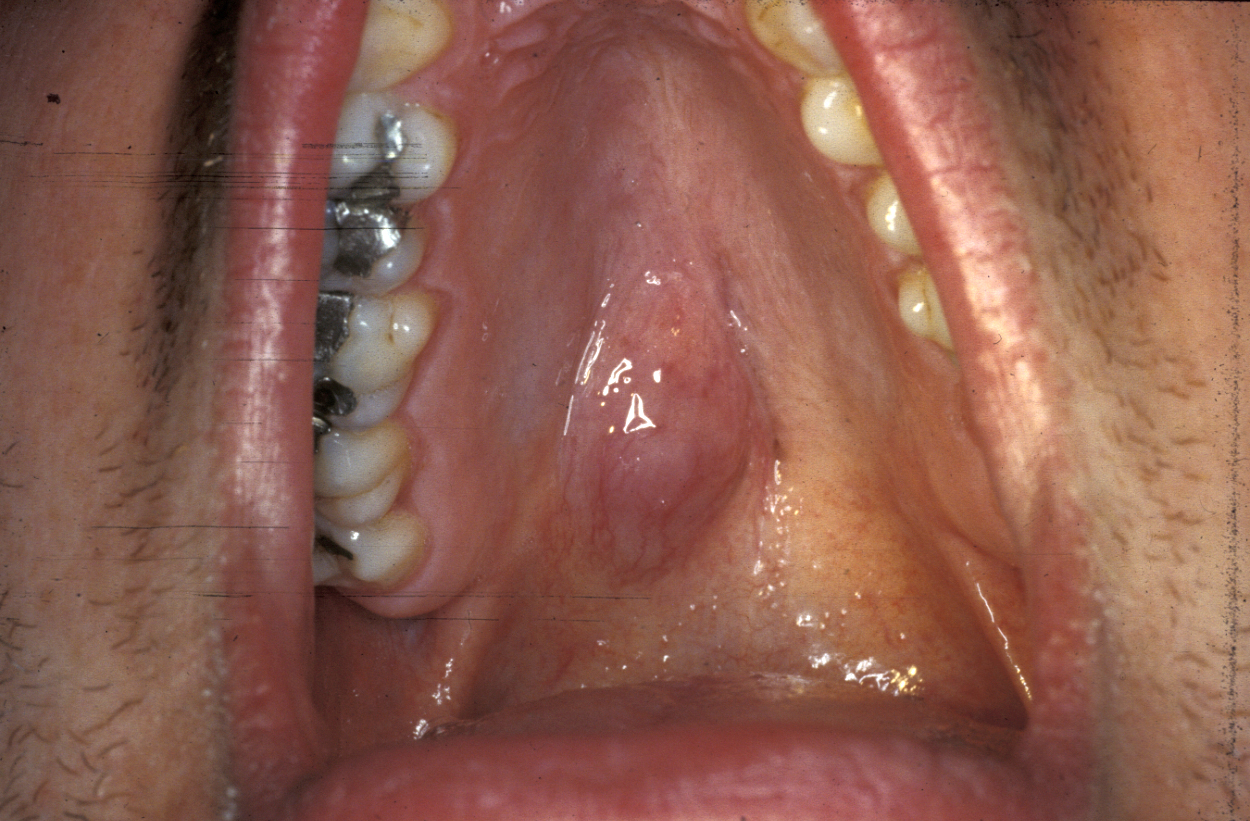

Another location where salivary gland pleomorphic adenoma may occur is in the palate area, most often at the junction of hard and soft palates (see Figure 7).

Figure 7: Palatal pleomorphic adenoma arising at a typical site.

Figure 8: Excision of palatal pleomorphic adenoma by using a cleft palate gag to aid access. Subperiosteal stripping provides an adequate margin and heals well by allowing simple granulation to occur.

For all tumours which overlay the hard palate, simple subperiosteal excision with a mucosal margin is adequate (see Figure 8). Healing by secondary intention (leaving the wound as is) of the palate is excellent and can be achieved by using a dressing plate with a sedative and soothing dressing. If the tumour extends into the soft palate, the capsule of the tumour can be elevated from the underlying levator aponeurosis (a thin structure that connects the levator muscle (the muscle responsible for lifting up the soft palate when saying ‘ahhh’) . The soft palate defect will granulate with good functional result. If the levator aponeurosis is breached, however, this has to be repaired and should be reconstituted with vascularised tissue, such as a buccal fat pad flap, or a temporoparietal fascial flap.